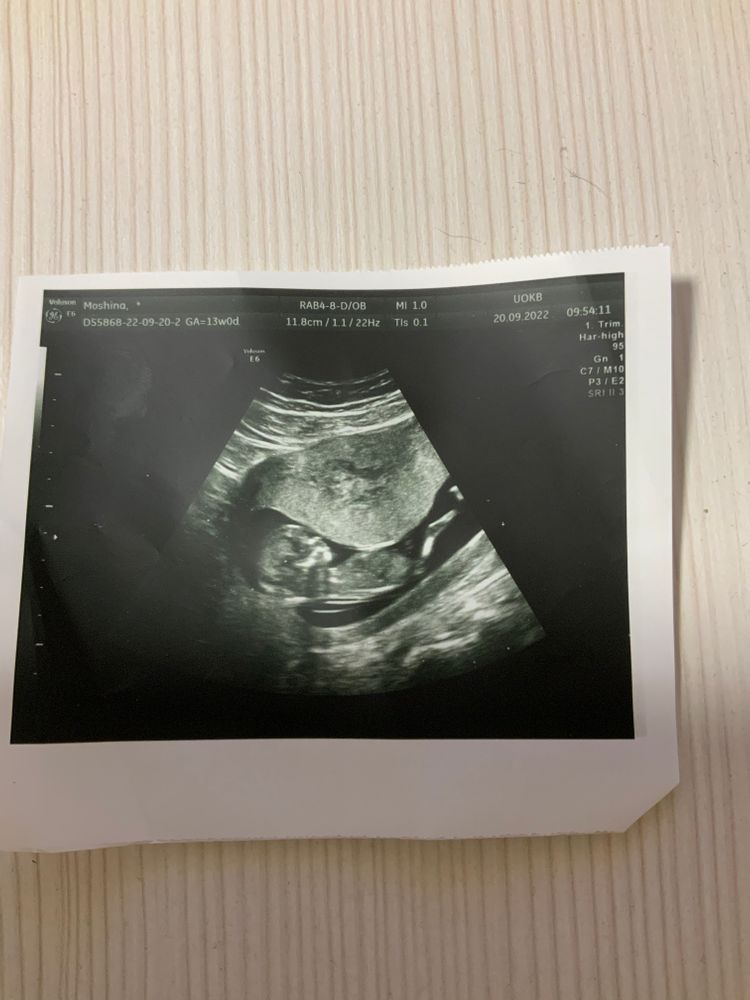

Показатели в норме. Срок 12+6

Врач УЗД ну очень быстро все делала, комментариев никаких не дала…

Пока делали узи, пыталась разглядеть, никаких бугорков не разглядела 😁😁😁

Ну если то, что я вижу на фото половой бугорок, то я голосую за девочку) чсс какой?